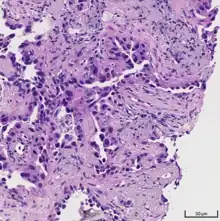

Histopathology

Adenocarcinoma of the lung tends to stain mucin positive as it is derived from the mucus-producing glands of the lungs. Similar to other adenocarcinoma, if this tumor is well differentiated (low grade) it will resemble the normal glandular structure. Poorly differentiated adenocarcinoma will not resemble the normal glands (high grade) and will be detected by seeing that they stain positive for mucin (which the glands produce). Adenocarcinoma can also be distinguished by staining for TTF-1, a cell marker for adenocarcinoma.[29]

As discussed previously, the category of adenocarcinoma includes are range of subtypes, and any one tumor tends to be heterogeneous in composition. Several major subtypes are currently recognized by the World Health Organization (WHO)[1] and the International Association for the Study of Lung Cancer (IASLC) / American Thoracic Society (ATS) / European Respiratory Society (ERS):[30][31][32] lepidic predominant adenocarcinoma, acinar predominant adenocarcinoma, papillary predominant adenocarcinoma, micropapillary predominant adenocarcinoma, solid predominant adenocarcinoma, and solid predominant with mucin production. In as many as 80% of these tumors, components of more than one subtype will be recognized. Surgically resected tumors should be classified by comprehensive histological subtyping, describing patterns of involvement in increments of 5%. The predominant histologic subtype is then used to classify the tumor overall.[2] The predominant subtype is prognostic for survival after complete resection.[33]

To reveal the adenocarcinomatous lineage of the solid variant, demonstration of intracellular mucin production may be performed. Foci of squamous metaplasia and dysplasia may be present in the epithelium proximal to adenocarcinomas, but these are not the precursor lesions for this tumor. Rather, the precursor of peripheral adenocarcinomas has been termed atypical adenomatous hyperplasia (AAH).[10] Microscopically, AAH is a well-demarcated focus of epithelial proliferation, containing cuboidal to low-columnar cells resembling club cells or type II pneumocytes.[10] These demonstrate various degrees of cytologic atypia, including hyperchromasia, pleomorphism, prominent nucleoli.[10] However, the atypia is not to the extent as seen in frank adenocarcinomas.[10] Lesions of AAH are monoclonal, and they share many of the molecular aberrations (like KRAS mutations) that are associated with adenocarcinomas.[10]